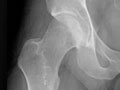

You may also have an X-ray (such as an X-ray of the hip or knee) or other imaging tests to check for joint damage.